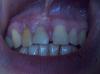

taurus1010 Опубликовано 20 сентября, 2012 Поделиться Опубликовано 20 сентября, 2012 Уважаемые хирурги!Хотел бы узнать ваше авторитетное мнение по моему случаю.1. Детская травма - выбили 11-ый зуб в 10-летнем возрасте.2. Через 15 лет почувствовал давление в области. Сфотографировал -- киста над 11,12. (См. снимок "2003 г").3. с 2003 по 2007 было произведено четыре резекции верхушек корней без подсадки костного материала. Четыре, т.к. были свищи, болевые ощущения, недомогание.4. После последней резекции с 2007-2008 года состояние стабилизировалось. Не беспокоило. (См. снимок "дек 2010_контрольный")5. В августе 2012 происходит продольный перелом 12 зуба (жесточайше кусанул замерзшую в камень изюмину в мороженом, блин...). Обломок лицевой части коронки уходит на 3 мм. под десну. (См. цветные фото)6.Предложено: а)удаление 12, 11 зубов, чистка кистозной зоны и одномоментная имплантация (+подсадка синт.костного материала от Альфа Био) с немедленным временным протезированием на временных абатментах с выведением коронок из прикуса и шинированием конструкции на период остеоинтеграции посредством объединения временных коронок между собой. б)Также есть предложение классическое: удаление 11,12-->аутокостная пластика с мембраной+ бабочка--> 3 месяца-->контроль-->имплантация+ бабочка--> 6 мес.--->контроль--> постоянное протезирование безметалловой керамикой. Вопрос:1.Какой план лечения по вашему мнению будет оптимальным с учетом эстетически важной зоны?(Классическая: аутокостная пластика+бабочка+отсроченная имплантация ч/з 3 мес.либо одномоментная имплантация + бабочка, либо одномоментная имплантация + временные коронки)2. Показана ли мне немедленная имплантация после удаления зубов с учетом истории болезни (хронический процесс)?3. Возможно ли при одномоментной имплантации провести кюретаж с высокой эффективностью, чтобы возможная инфекция не привела в отдаленной перспективе к потере имплантата?4. Сравнимы ли будут отдаленные результаты немедленной и классич.имплантации в моем случае?5. Бабочка. Испортит ли она мне междесневые сосочки? Есть противоположные мнения. Благодарю. Ссылка на комментарий